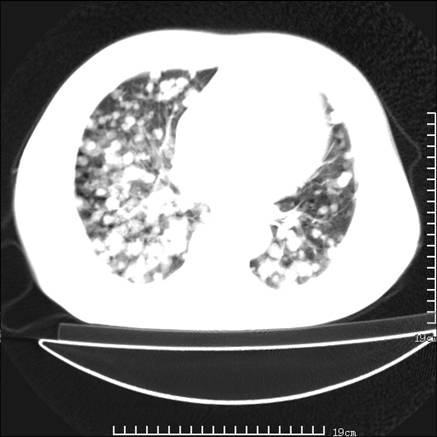

张男,75岁,干咳半年余,小便不利二年,b超检查前列腺增大,未见明显肿块;前列腺癌血生化检查多项指标明显增高。

双肺内多发转移瘤,纵膈淋巴结转移。来源前列腺?建议盆腔mri进一步检查。

双肺转移满了。

两肺广泛转移瘤。